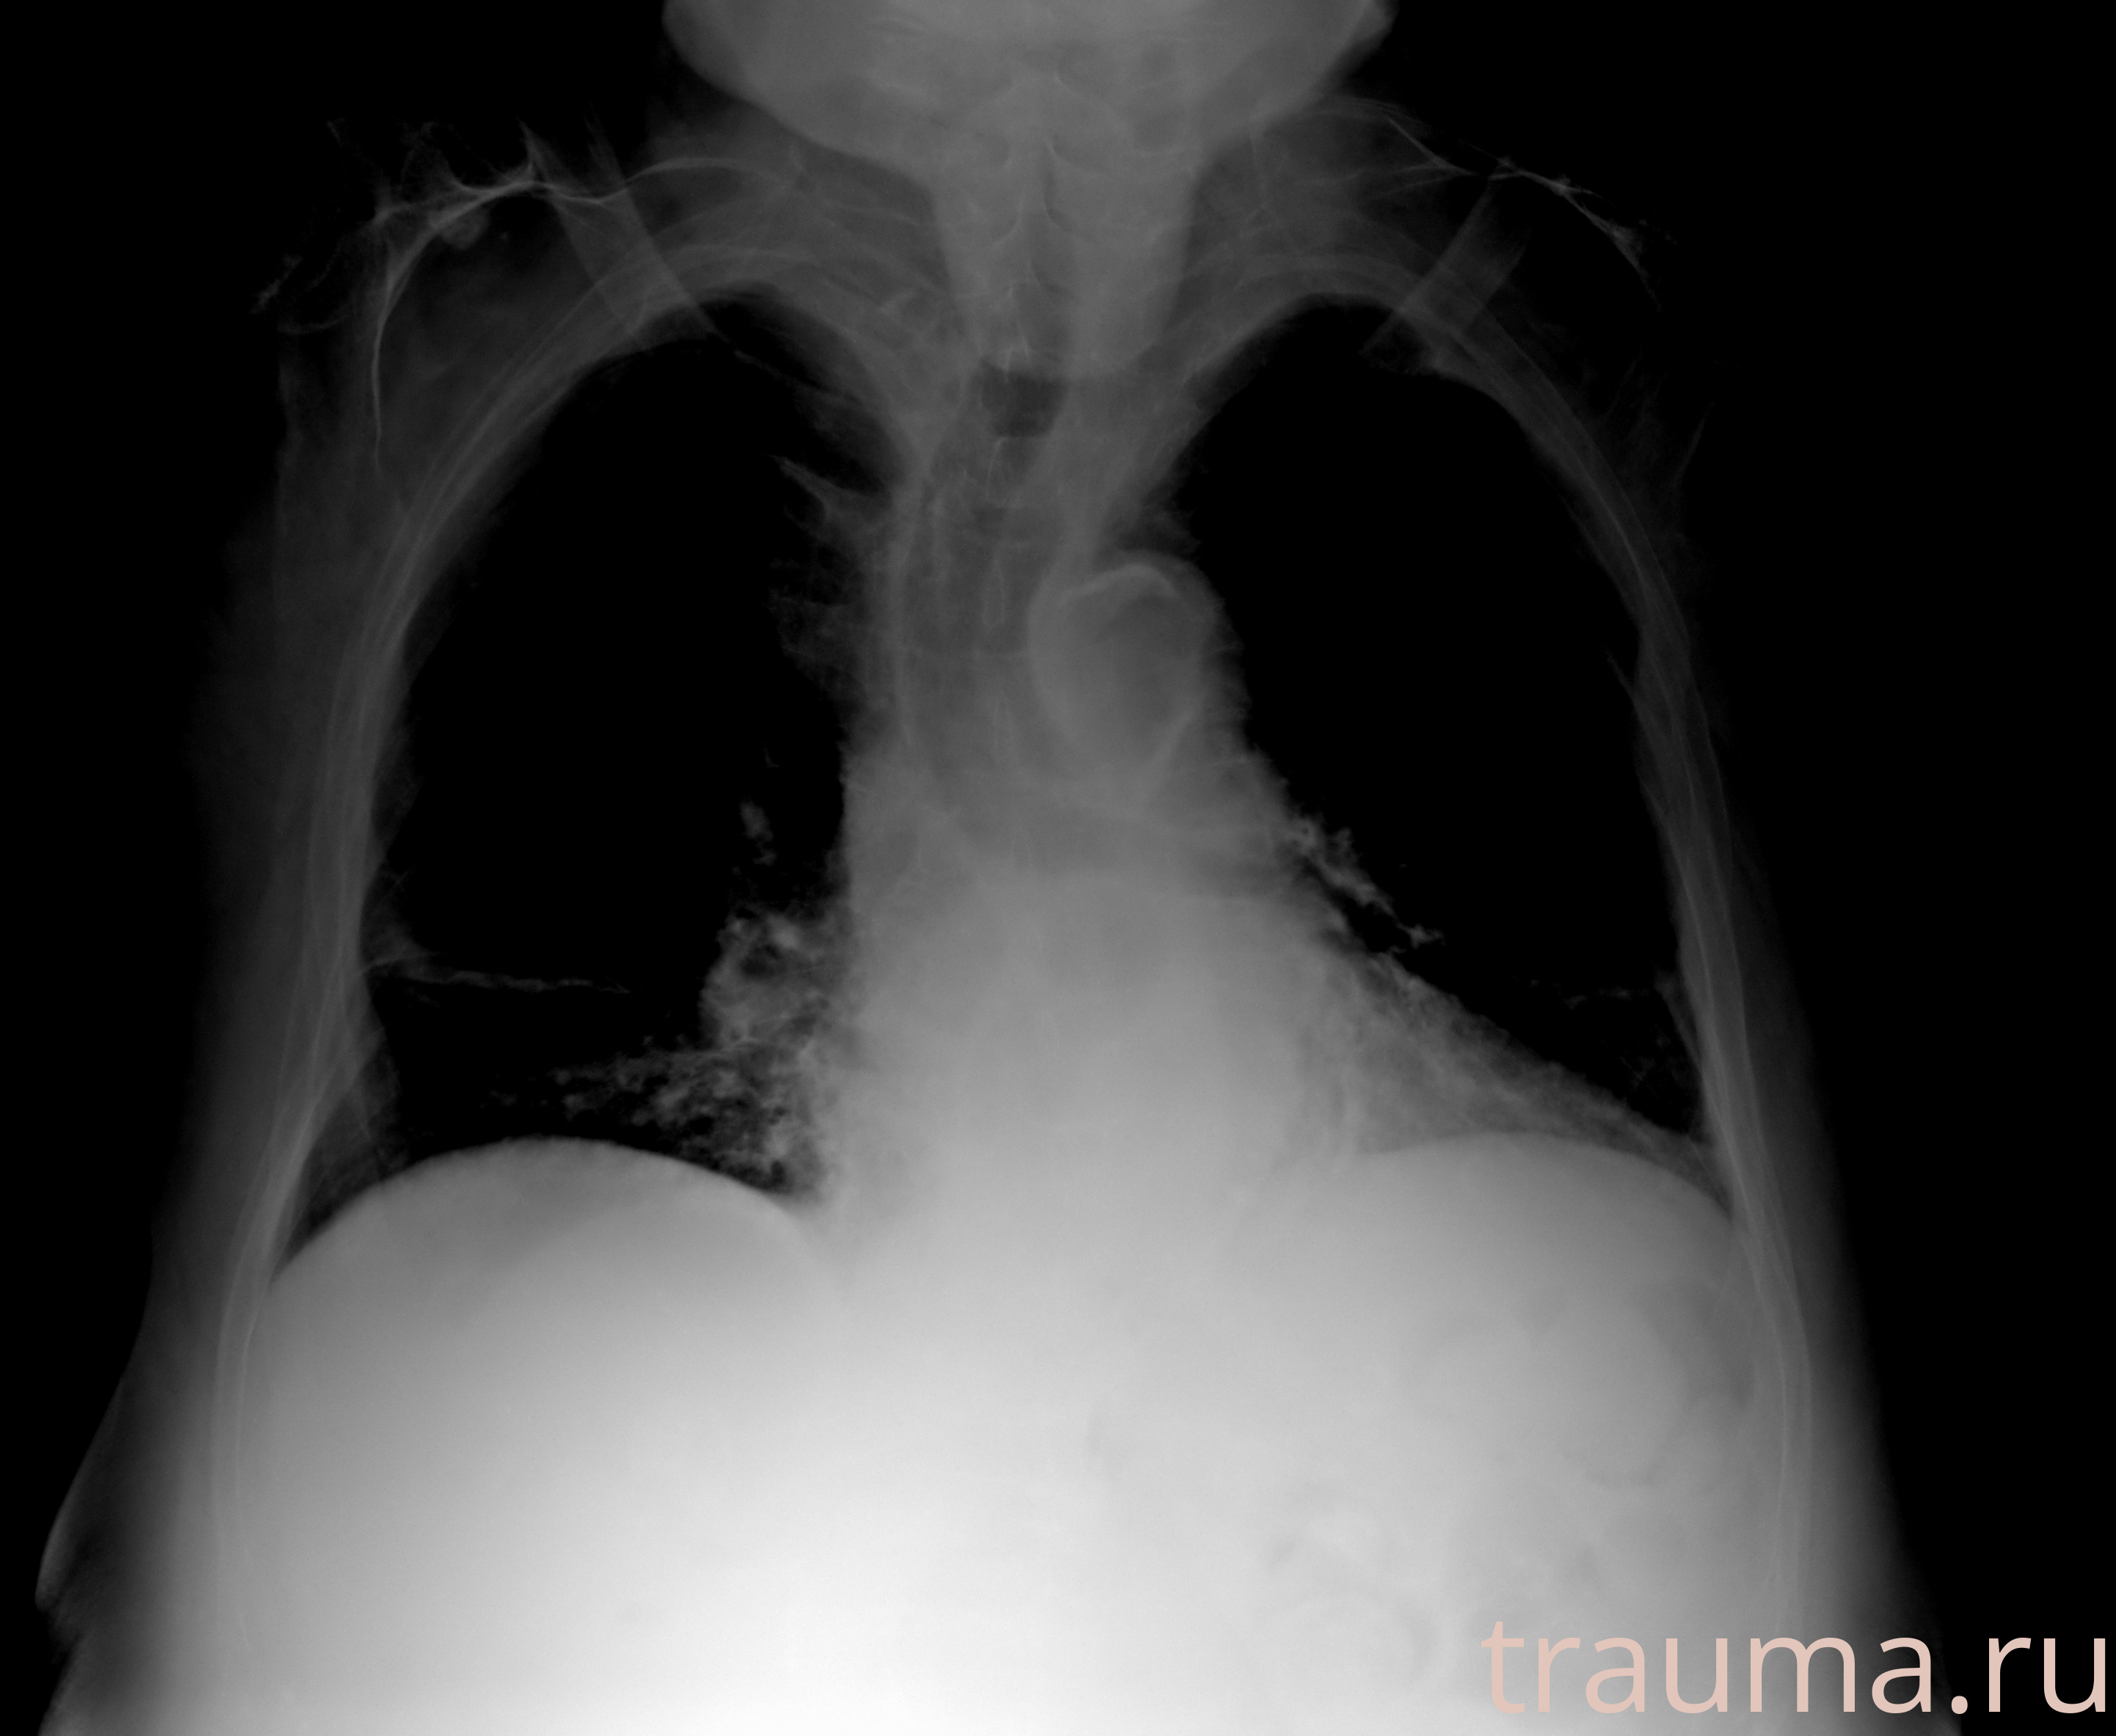

Перелом 3-5 ребер слева

Рентген на дому: по вашему адресу приезжает врач-рентгенолог, травматолог-ортопед с мобильным рентгеновским аппаратом, проводит диагностику травмы или заболевания, делает необходимые рентгенограммы, дает рекомендации по дальнейшему лечению. Получить качественные снимки в домашних условиях возможно благодаря уникальной методике, разработанной МосРентген Центром для института  Склифосовского